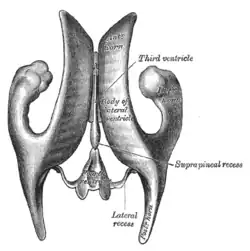

3D Model of ventricular system Scheme showing relations of the ventricles to the surface of the brain.

Scheme showing relations of the ventricles to the surface of the brain. Drawing of a cast of the ventricular cavities, viewed from above.

Drawing of a cast of the ventricular cavities, viewed from above. View of ventricles and choroid plexus